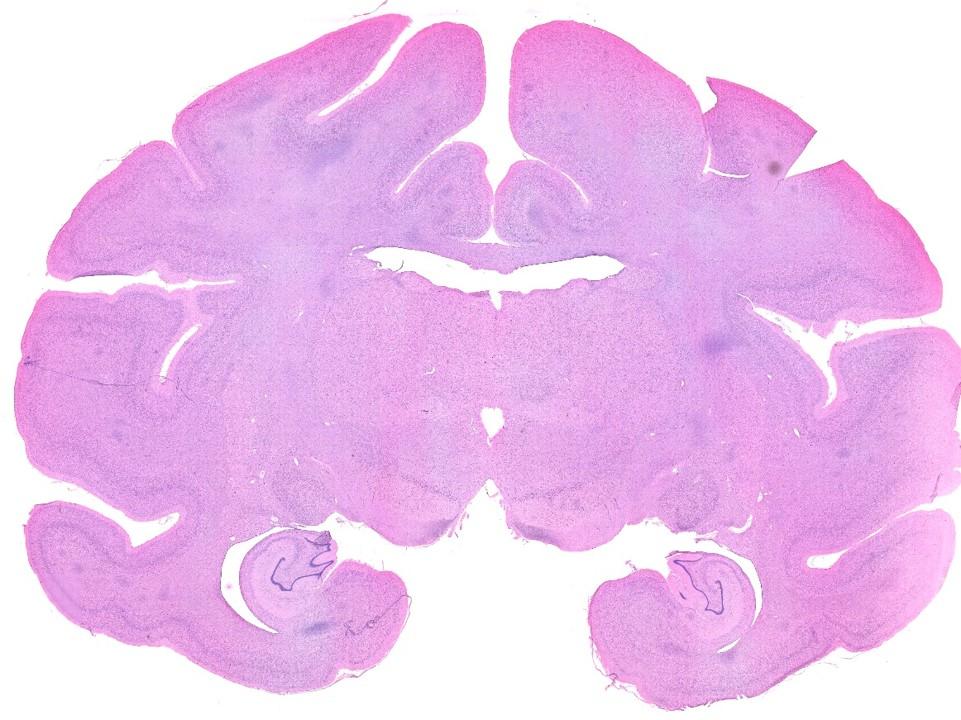

TissueFAXS第8代系統整合了最新的AI影像識別技術,配備高靈敏度sCMOS相機和多色LED光源,支援從組織形態學到分子病理學的全方位分析。系統可同時進行明場H&E染色、免疫螢光、FISH檢測等多種染色技術,為精準醫學和藥物開發提供強大的影像證據。

- 多模式成像:明場、螢光、相差、暗場、偏振光等多種成像模式